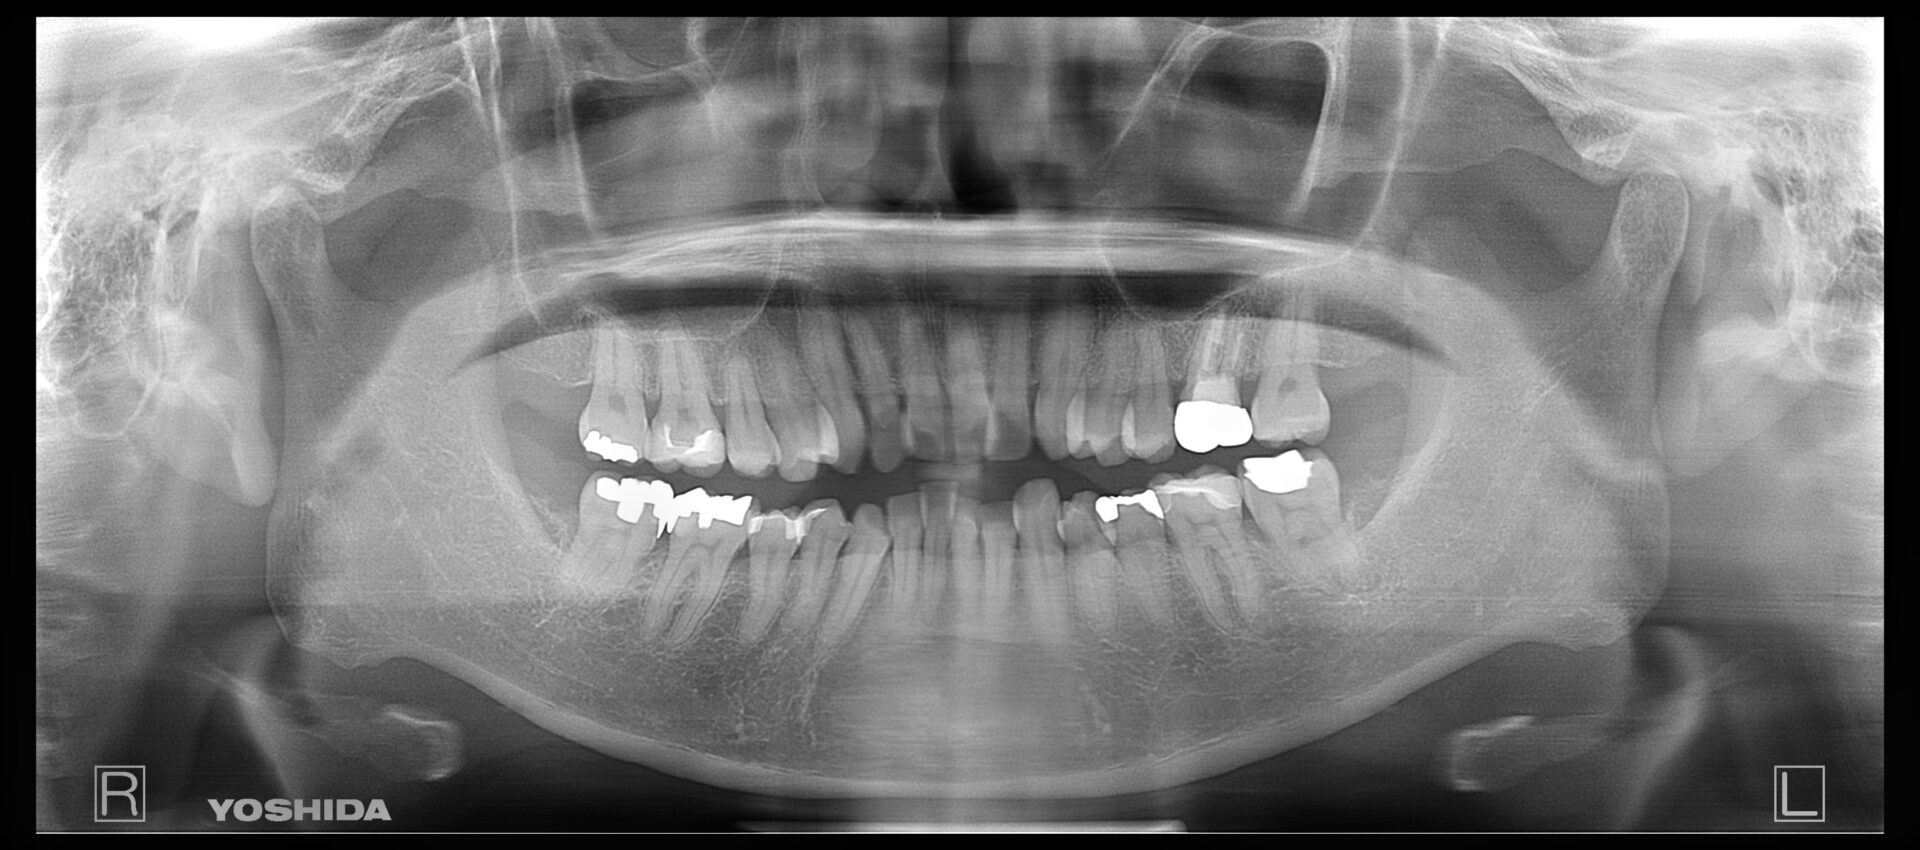

60代男性

R5.8

右下4番破折の疑い

R5.12

右下4番抜歯後経過観察

画像

R6.12

インプラント埋入後、上部の被せ物を被せました

費用 約43万円

治療期間 1年4ヶ月

右下4番にフィステルが頻繁にできており、他院では抜歯のみと説明を受け、他の治療を検討できないかと当院にお越しになられました。

根管治療を数回行い、フィステルの出現は小さくなり頻度も減ったが抜歯が最善との判断に至りました。

抜歯をし、インプラントをご希望されていたのでしっかり5ケ月かけて経過を観察し、インプラントオペを行いました。